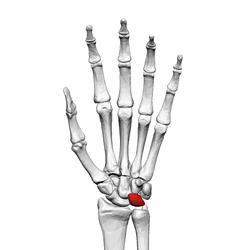

Lunate bone (left hand) 01 palmar view.png

Left hand anterior view (palmar view). Lunate bone shown in red.

The lunate bone (semilunar bone) is a carpal bone in the human hand. It is distinguished by its deep concavity and crescentic outline. It is situated in the center of the proximal row carpal bones, which lie between the ulna and radius and the hand. The lunate carpal bone is situated between the lateral scaphoid bone and medial triquetral bone.

The lunate is a crescent-shaped carpal bone found within the hand. The lunate is found within the proximal row of carpal bones. Proximally, it abuts the radius. Laterally, it articulates with the scaphoid, medially with the triquetral, and distally with the capitate. The lunate also articulates on its distal and medial surface with the hamate bone.[1]:708[2]

Bone

The proximal surface of the lunate bone is smooth and convex, articulating with the radius. The lateral surface is flat and narrow, with a crescentic facet for articulation with the scaphoid. The medial surface possesses a smooth and quadrilateral facet for articulation with the triquetral. The palmar surface is rough, as is the dorsal surface. The dorsal surface is broad and rounded. The distal surface of the bone is deep and concave.[3]